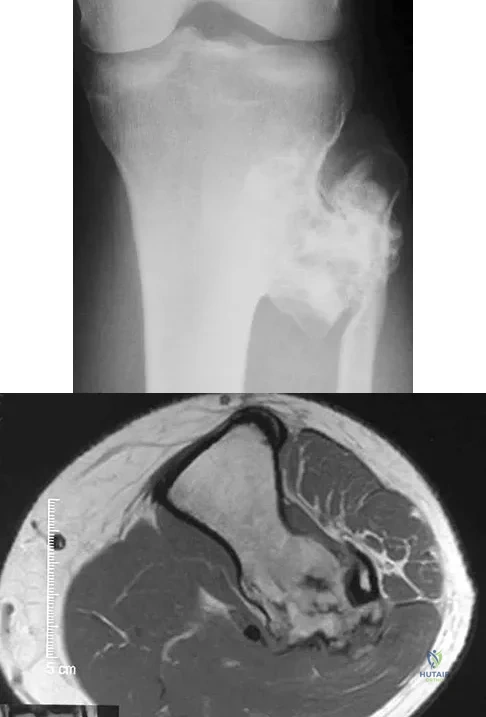

Figures 26a and 26b show the radiograph and MRI scan of a 22-year-old man with knee pain. What is the most likely diagnosis?

Explanation